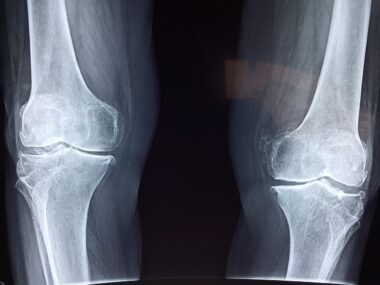

Bone health is crucial for overall physical wellness, often overlooked in fitness programs. By integrating technology into exercise regimens, individuals can effectively monitor their bone health progress. Technologies such as wearable devices, mobile applications, and advanced imaging techniques provide valuable data to help users understand their bone density and strength. Utilizing these technologies in fitness programs can significantly enhance motivation and adherence to workout plans. With real-time feedback, participants can adjust their routines based on their unique bone health metrics, preventing injuries and optimizing performance. Furthermore, fitness trainers can leverage this information to tailor exercises that improve bone health specifically, ensuring a comprehensive approach. In collaboration with healthcare professionals, fitness enthusiasts can align their exercise strategies to support both bone health and overall physical fitness. This symbiotic relationship between fitness technology and health monitoring is continually evolving, promising better outcomes for individuals seeking to improve their bone health. Embracing these advancements can lead to a more informed and proactive approach, promoting longevity and quality of life as people age. In combination with proper nutrition and exercise, technology can play a pivotal role in maintaining strong and healthy bones.